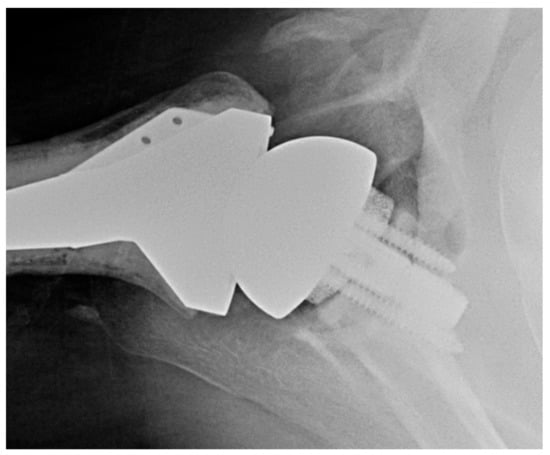

2.3. Inlay versus Onlay Glenoid Components

3.2.2. Inlay vs. Onlay Implants

3.2.3. Vitamin E Polyethylene Implants